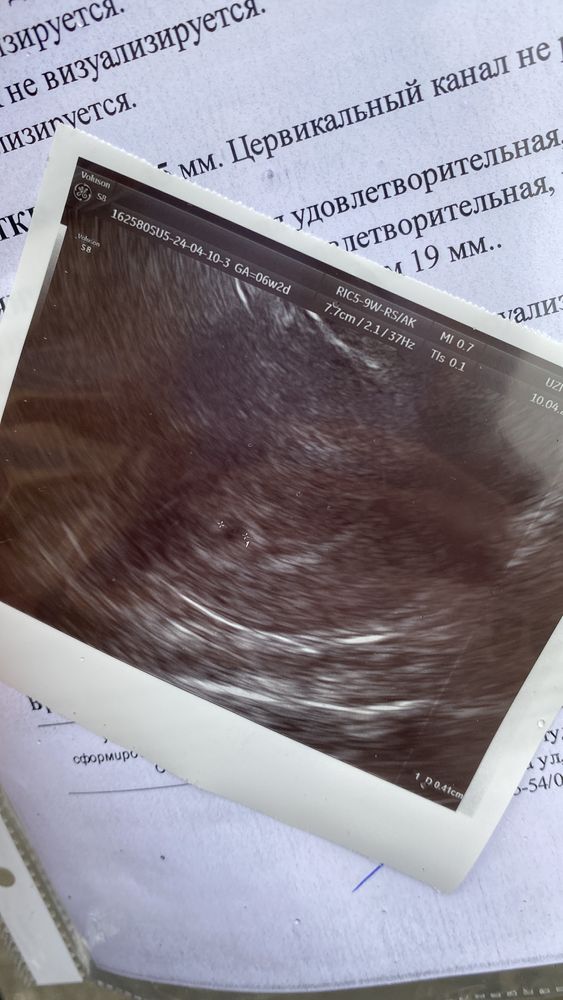

Мы ещё совсем маленькие, но растем , сегодня была на узи первый раз, аж на слезы пробила когда мы с тобой встретились❤️